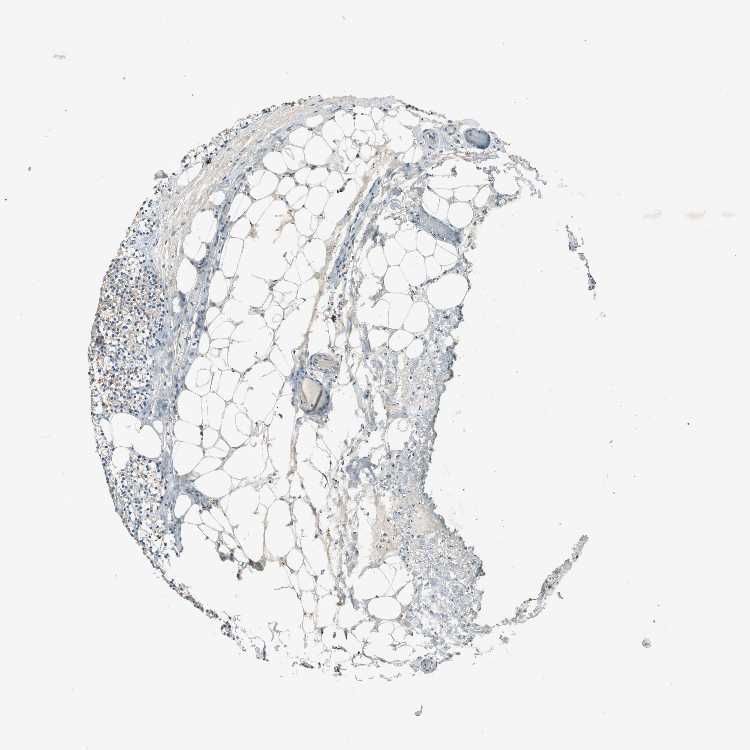

PARATHYROID GLAND - Antibody stainingi

Antibody staining in the annotated cell types in the current human tissue is reported as not detected, low, medium, or high, based on conventional immunohistochemistry profiling in selected tissues. This score is based on the combination of the staining intensity and fraction of stained cells.

Each image is clickable and will lead to virtual microscopy that enables deeper exploration of all samples and also displays staining intensity scores, fraction scores and subcellular localization as well as patient and tissue information for each sample.

Antibody HPA006873

Glandular cells Low